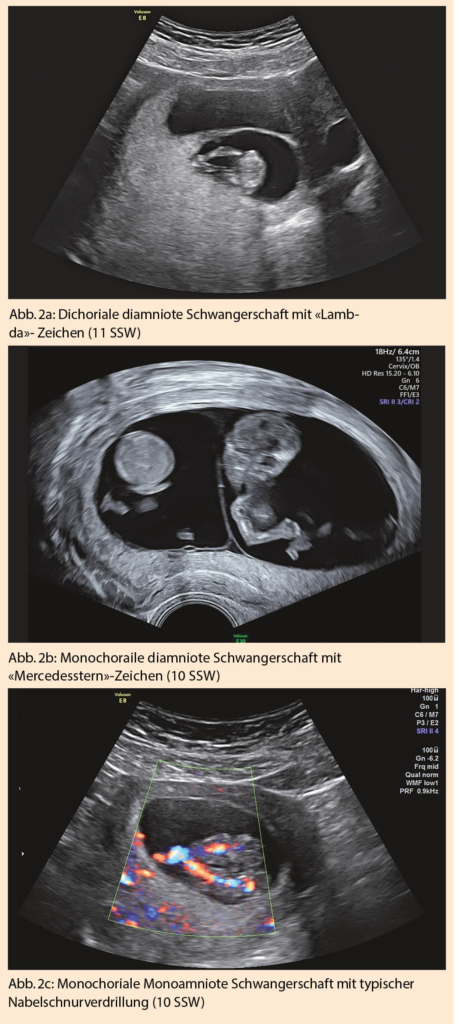

Teilt sich die Zygote erst nach dem 13. Tag post conceptionem, resultieren siamesische Zwillinge (Abb. 3a). Art und Ausmass der Verbindung kann sehr variieren und geht entsprechend mit unterschiedlichsten Prognosen einher. Wichtig sind eine frühzeitige Diagnose und eine entsprechende Beratung des Paares.

Eine weitere für monochoriale Zwillingsschwangerschaften spezifische Diagnose des ersten Trimesters ist die TRAP (twin reversed arterial perfusion)-Sequenz. Typischerweise fehlt hier bei einem Zwilling das Herz und die obere Extremität (=Akardius acranius). Eine arterio-arterielle Anastomose, vom zweiten, ‘pumpenden Zwilling’ kommend, gewährleistet die Durchblutung des Akardius acranius. Mit dem Farbdoppler lässt sich dieser umgekehrte Blutfluss gut darstellen (Abb.3 b). Die Mortalität für den pumpenden Zwilling liegt bei >50 %. Eine rechtzeitige Trennung der beiden Kreisläufe, meist mittels Lasertherapie, kann rettend sein (11).